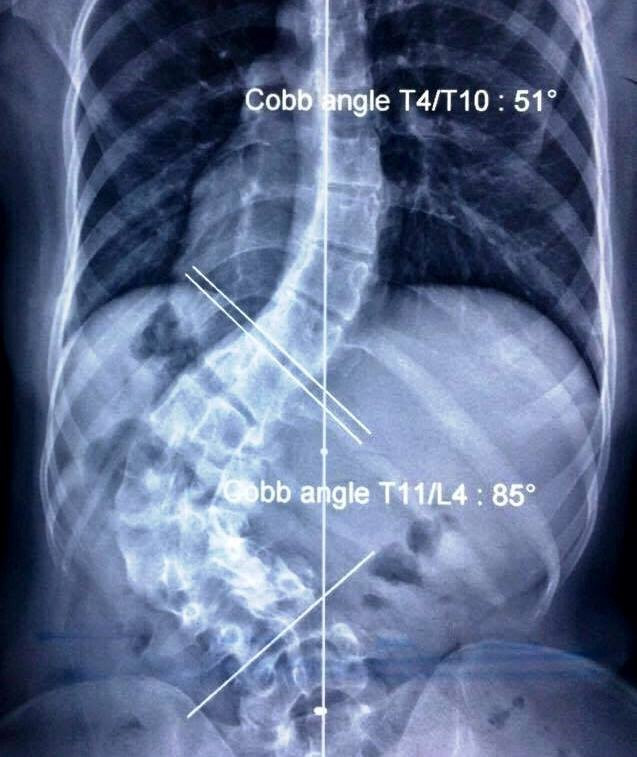

Cột sống bị cong vẹo của cô sinh viên được chụp qua X-quang. (Ảnh: Hoài Nhơn)

PGS Võ Văn Thành cho biết, trường hợp của Phụng chưa được y văn thế giới ghi nhận. Sau khi tiếp nhận từ tháng 2, qua hội chẩn chuẩn bị đánh giá khả năng thành công, bác sĩ Thành đã quyết định mổ sau 4 tháng.